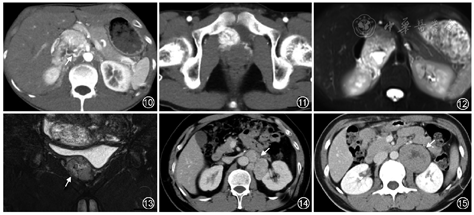

2.腹膜后肾上腺外副神经节瘤:好发于30~50岁患者,无明显性别差异,多为功能性肿瘤;占腹膜后肿瘤的1%~3%,可发生于腹膜后任何部位,好发于肾动脉至腹主动脉分叉水平的主动脉旁区域,最常见于Zuckerkandl体(图2,3),即肠系膜下动脉起始处与腹主动脉分叉之间[3]。不同部位肾上腺外副神经节瘤的影像学特征类似。良性肿瘤体积常较小,密度均匀。较大的肿瘤呈椭圆形或分叶状边界清楚的软组织肿块,常伴坏死和出血(图2~7),有时可见出血所致液液平面(图3)。副神经节瘤为富血供肿瘤,增强后明显强化,动脉期显著,肿块周围或实性成分内可见迂曲增粗的肿瘤血管[6, 7]。少数因肿瘤内大量出血或坏死呈低强化或无强化(图8,9)。钙化较常见,发生率约15%。肿瘤T1WI上呈等或低信号,内部出血区呈高信号(图9);T2WI上信号不均匀,可呈显著高信号;表观扩散系数相对于神经鞘瘤和颈部副神经节瘤更高[8]。此外,应仔细观察有无多发副神经节瘤(图10, 11, 12, 13)。

3.恶变、转移及预后:副神经节瘤具有一定的恶变及转移潜能,恶变率2%~10%,恶性肿瘤常较大,内部见低密度坏死区。恶性副神经节瘤可通过淋巴或血行转移播散至区域淋巴结、骨、肝、肺等部位。腹膜后肾上腺外副神经节瘤侵袭性更强,多达42%的病例发生转移[3],而嗜铬细胞瘤转移发生率仅2%~10%。不存在嗜铬性组织的部位如果出现肿瘤灶,则诊断为转移性病灶。组织病理学难以界定良恶性,是否发生血管与周围结构侵犯或远处转移是诊断恶性副神经节瘤的主要可靠依据。CT、MRI、核医学MIBG成像和PET/CT可用于分期及评价转移性病灶[9](图14)。预后主要取决于肿瘤生长的部位、有无转移及相关遗传性综合征[1, 2, 5]。

神经鞘瘤为起源于施万细胞的良性肿瘤,占腹膜后肿瘤的4%~6%[10],临床上常无症状而影像学检查偶然发现。女性较男性更常见,常见于中青年(20~50岁最多见),好发部位为邻近肾脏的脊椎旁或骶前腹膜后间隙。和副神经节瘤一样,也可沿脊椎旁的交感神经链分布。体积小的神经鞘瘤CT和MRI上表现为边界清楚的圆形或椭圆形密度均匀的肿块;体积较大时不均质、常发生囊变(图15)。钙化常见,可呈点状、斑点状或曲线状。血管侵犯少见。腹膜后肿瘤蔓延至椎间孔及椎管内出现典型哑铃征,提示周围神经鞘瘤。

2.平滑肌肉瘤:起源于腹膜后平滑肌组织或腹膜后大静脉管壁,为腹膜后第二常见肉瘤(约占28%),其发病年龄较神经源性肿瘤患者更大,且预后更差。平滑肌肉瘤最常见生长方式为完全血管外生长的肿瘤,少数肿瘤呈血管外和血管内同时受累,完全血管内生长(常发生于下腔静脉)罕见[12]。组织病理学可见典型交错排列、边缘锐利的梭形细胞束。临床常无症状,常为影像学偶然发现。肿瘤较大时可引起临床压迫性症状。影像上通常表现为较大的边界不清的软组织肿块,内部可见坏死、出血或囊变区(图16)。钙化少见,可见于罕见的骨肉瘤分化病例。

3.Castleman病:即巨淋巴结增生症,病因不明,以淋巴细胞增殖为特征,约12%病例累及腹膜后。临床上可分为局灶型和弥漫型,病理上分为透明血管型、浆细胞型、人类疱疹病毒相关和多中心型[13]。局灶型Castleman病主要为透明血管型,手术切除预后良好。弥漫型多见于浆细胞型,预后差,需要系统性治疗。局灶型好发于30~50岁患者,表现为较大的孤立性软组织肿块,可伴周围卫星灶,边界清晰,内部可见斑点状钙化(图17)、囊变或坏死区。肿块T1WI呈等信号、T2WI呈高信号,增强后动脉期明显强化,通常均匀强化,并持续至延迟期(图18)。可伴肝脾肿大、腹腔积液、腹膜后筋膜增厚。